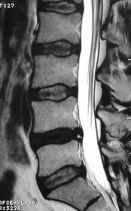

Ağustos 2023       Eski lomber stabilizasyon sistemi altında kırık (ikinci olgu)